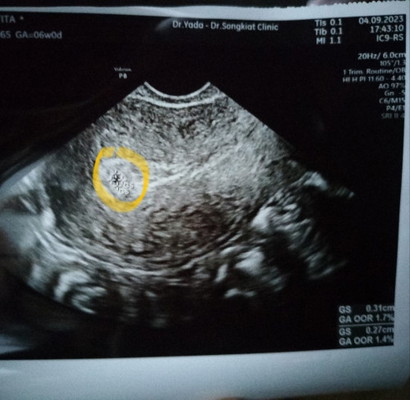

ภาพอัลตราซาวด์ตอนน้องได้6w1dคะ ตอนนี้10wแล้ว ท้องยังอ่อนคุณแม่รออีกสักนิดนะคะ

ถ้านับจากประจำเดือนครั้งสุดท้ายตอนนี้ก็6วีค1วันคำนวนตามแอพ แต่เมื่อวานตอนฉี่มีเลือดไหลออกมาทุกครั้งเวลาฉี่ เลยไปหาหมอ ผลซาวไม่เจอถุงตั้งครรภ์ มีเพียงจุดเล็กๆขนาดประมาณ2มิลหมอเลยไม่ฟันธงว่าใช่ถุงตั้งครรภ์ไหม หมอเลยตรวจดูค่าโฮโมนจากเลือดผลคือตั้งครรภ์แต่อาจจะเสี่ยงแท้ง วันหัสหมอเลยนัดเจาะเลือดติดตามใหม่ว่าแนวโน้มจะเป็นไปทางแนวไหน ตอนนี้เครียดมากเลยค่ะอยากทราบที่ไม่เจอถุงเพราะอะไร จะเพราะอายุครรภ์ไม่ถึง6ตามแอพไหม ตอนนี้กังวลไปหมดแล้ว ท้องแรกไม่เคยเป็นแบบนี้เลยค่ะ

ถ้านับจากประจำเดือนครั้งสุดท้ายของบ้านนี้ อายุครรภ์ประมาณ 7-8 วีค แต่ครั้งแรกซาวด์หน้าท้องไม่เจอ ครั้งที่2 เมื่อวันพุธซาวด์ทางมดลูกคุณหมอเจอถุงเล็กมากค่ะ คุณหมอบอกว่าน่าจะประมาณ 5 วีคเองค่ะ คุณหมอนัดไปซาวด์อีกที 22 นี้ค่ะ ได้แต่ภาวนาขอให้น้องสมบูรณ์แข็งแรงค่ะ❤️